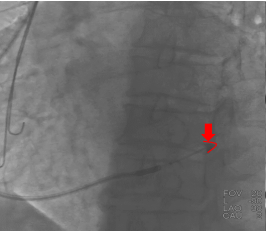

鞘管进入窦口之后冒烟显示静脉有部分狭窄,球囊造影的时候也出现阻力,造影显示近端有瓣,无法通过电极,最终利用球囊扩张,让电极顺利通过静脉瓣。

图五&六 造影发现有静脉瓣